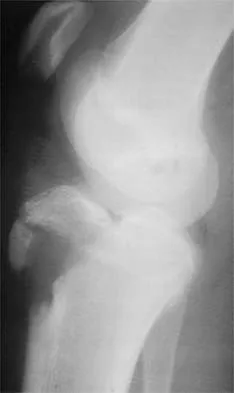

Question 20

Figure 35 shows the lateral radiograph of a 15-year-old basketball player who felt a dramatic pop in his knee when landing after a lay-up. The patient reports that he cannot bear weight on the injured extremity. Management should consist of

Explanation